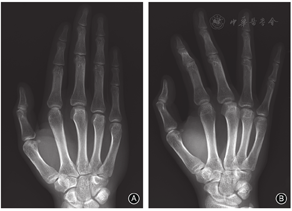

保守治疗2个月后患者右手局部疼痛症状逐渐缓解,口服镇痛药物逐渐减量,4个月后疼痛症状明显改善,右手第3、4掌指关节屈伸活动度逐渐增加,X线片示掌骨头骨质坏死病变无明显进展。半年后门诊复查,患者右手无明显疼痛症状,右手第3、4掌指关节屈伸活动约为85°-10°,右手抓握力约为健侧的90%。治疗后2年,右手各指疼痛评分均为0分、DASH评分为0,右手3、4指掌指关节屈伸活动恢复正常(88°-0°),与对侧无明显差异;无明显骨擦感、骨擦音,右手抓握力为健侧的105%,功能恢复正常(图3)。X线片示右手各指掌指关节正常,第3、4掌骨头关节面变平明显改善、关节面基本恢复,局部骨质硬化改变消失,无明显骨质增生、关节退变表现(图4)。MRI示右手第3、4掌骨头无骨髓水肿挫伤表现,无关节积液,关节面平整,无明显塌陷破坏(图5),提示坏死掌骨头有关节重塑再生。